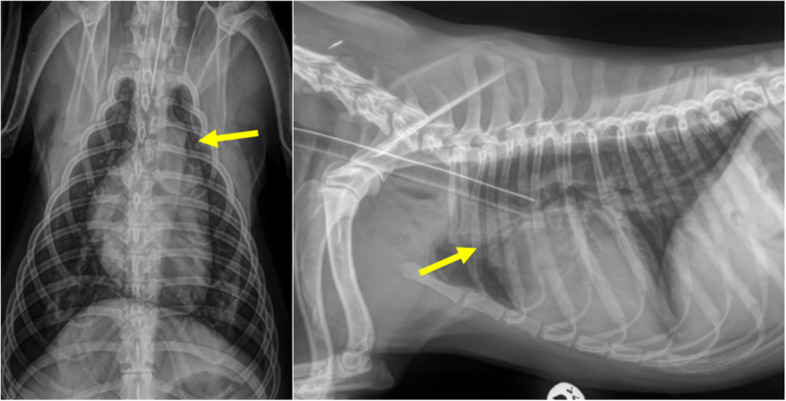

在麻醉前超声心动图评估中,一只3岁雌性塔特兰猎犬偶然诊断出左冠状动脉和肺动脉主动脉之间的血管通信(冠状动脉瘘)。考虑到患者的病史、临床检查和诊断成像,没有怀疑创伤和心内膜炎,这可能是导致这种疾病发展的原因。经胸超声心动图示左冠状动脉开口扩张,彩色及频谱多普勒示持续分流,诊断为冠状动脉瘘。通过计算机断层扫描证实了这一诊断。冠状动脉瘘在人类和动物中都是罕见的发现。据作者介绍,这是第一例犬左冠状动脉和肺动脉主动脉之间先天性瘘的临床报道。

A vascular communication between the left coronary artery and the main pulmonary artery (coronary fistula) was incidentally diagnosed in a 3-year-old female Tatran hound during a pre-anesthetic evaluation using echocardiography. Trauma and endocarditis were not suspected given the patient's history, clinical examination, and diagnostic imaging, which could have contributed to the development of this condition. Transthoracic echocardiography revealed dilation of the left coronary ostium, and continuous shunting on color and spectral Doppler was observed and this led to the diagnosis of coronary artery fistula. This diagnosis was confirmed through computed tomography. Coronary artery fistulas are infrequent findings in both humans and animals. According to the authors, this is the first reported clinical case of a congenital fistula between the left coronary artery and the main pulmonary artery in a dog.